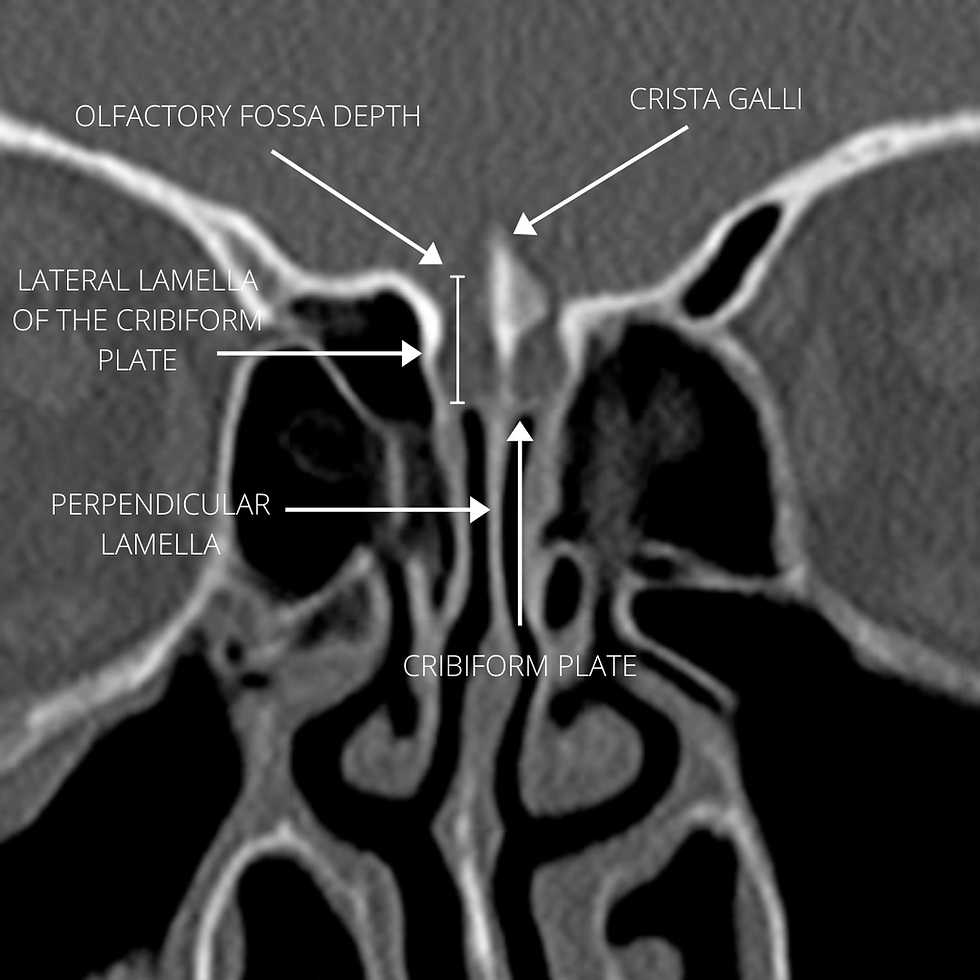

La lamina cribiforme es una zona de máximo riesgo por su delgadez y por la gran variabilidad anatómica. La configuración de la base del cráneo a este nivel en función de la altura de la lamela lateral y de la profundidad de la fosa olfatoria, define los 3 tipos de la clasificación de Keros: el tipo 1, con una lamela lateral de 1 a 3 mm y fosa olfatoria casi plana; el tipo 2, con una lamela lateral de 4 a 7 mm y una fosa olfatoria ligeramente profunda; y el tipo 3, donde la lamela lateral tiene de 8 a 16 mm, provocando una fosa olfatoria muy profunda.

El tipo 3 afortunadamente es el menos frecuente en la población ya que supone un mayor riesgo de complicaciones intracraneales, el tipo 1 es la configuración más favorable y el tipo 2 es la más frecuente.

La base de cráneo del etmoides está formada por la lámina cribiforme y el techo etmoidal, que es una extensión de la lámina orbitaria del hueso frontal. Estas 2 estructuras convergen en la lamela lateral de la lámina cribosa (LLLC), una zona de debilidad que es conocida por ser un sitio común de lesiones iatrogénicas de la base del cráneo, sugiriendo que mientras más profunda es la fosa olfatoria (Keros), esta es más susceptible al daño.